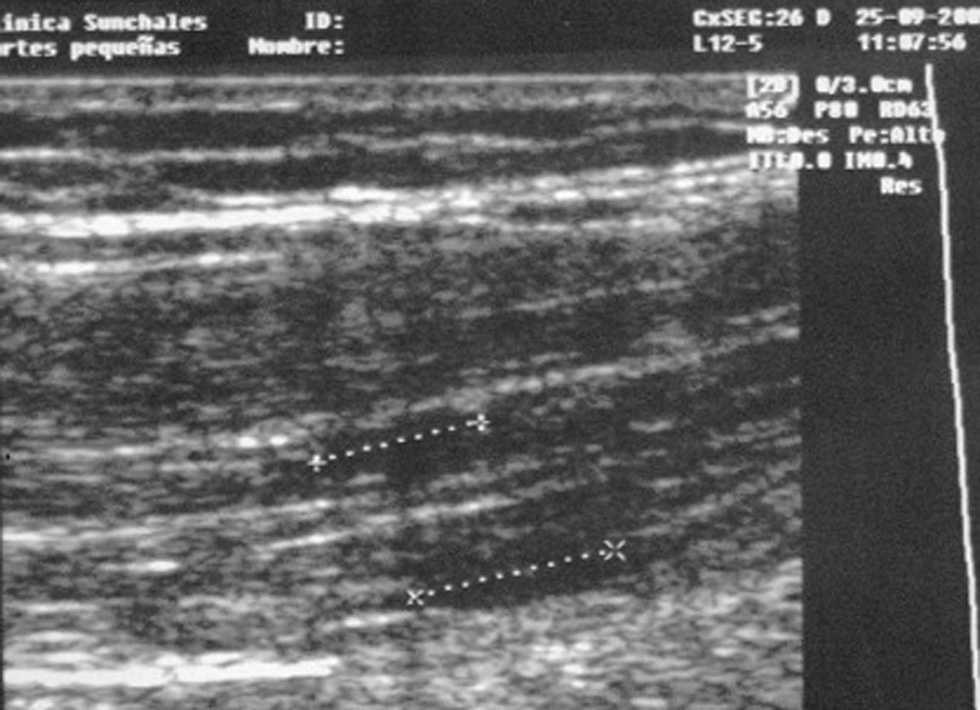

Fig. 6. Imagen ecográfica de lesión muscular fibrilar de 0,7 × 0,9 cm. en bíceps femoral derecho en su tercio medio de un basquetbolista profesional.